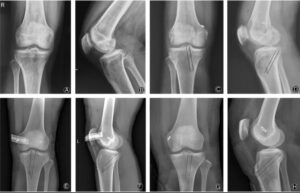

Diagnosis of Cartilage Defects

Accurate diagnosis involves a combination of:

- Clinical Examination: Assessment of pain, movement, and joint stability

- Imaging Tests:

- X-rays to evaluate joint space

- MRI for detailed cartilage assessment

- Arthroscopy: A minimally invasive procedure to directly visualize cartilage damage